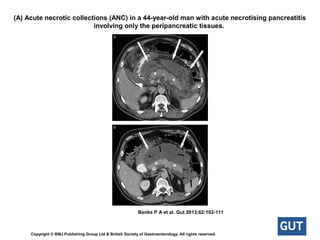

Necrotising pancreatitisNecrotising pancreatitis

About 5–10% of patients develop necrosis of the pancreatic

parenchyma, the peripancreatic tissue or both.

Necrotising pancreatitis most commonly manifests as necrosis

involving both the pancreas and peripancreatic tissues and less

commonly as necrosis of only the peripancreatic tissue, and

rarely of the pancreatic parenchyma alone.

(A) Acute necrotic collections (ANC) in a 44-year-old man with acute necrotising pancreatitis

involving only the peripancreatic tissues.

Banks P A et al. Gut 2013;62:102-111

Copyright © BMJ Publishing Group Ltd & British Society of Gastroenterology. All rights reserved.